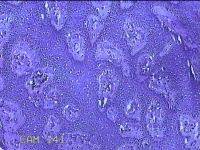

左侧臀部结节

性别

女

年龄

24岁

临床诊断

皮下结节

一般病史

发现左侧臀部结节1年余。

标本名称

大体所见

灰白暗红色带皮肤样结节0.7x0.3x0.2cm一个,表面糜烂,切开结节呈实性,切面灰白暗红色,质软。

图1